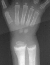

- Multiple rachitic deformities of the skeleton to include severe bowing

of the tibias bilaterally (45 degrees), pigeon chest (pectus carinatum),

thickened/widened wrists bilaterally and a trendelenberg gait on the left

side.

X-RAY STUDIES:

- "cupping" of the distal radius and distal femur

- widening of the physis

- angular deformities